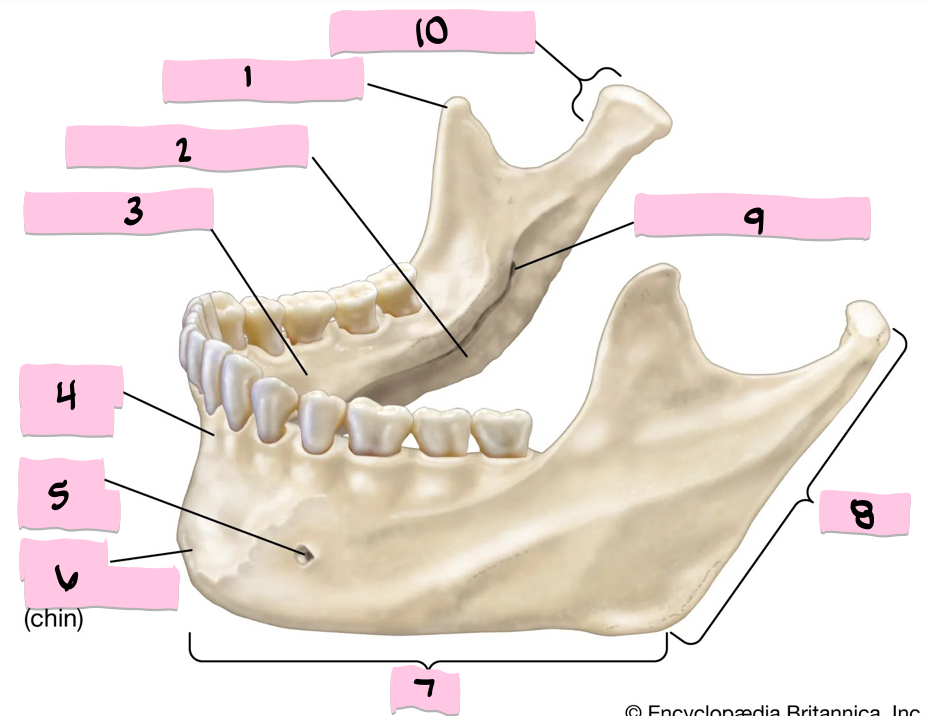

What is 1 pointing to?

Coronoid process

What is 2 pointing to?

Submandibular fossa

What is 3 pointing to?

Sublingual fossa

What is 4 pointing to?

Alveolar process

What is 5 pointing to?

Mental foramen

What is 6 pointing to?

Mental protuberance

What is 7 pointing to?

Body

What is 8 pointing to?

Ramus

What is 9 pointing to?

Mandibular foramen

What is 10 pointing to?

Condylar process